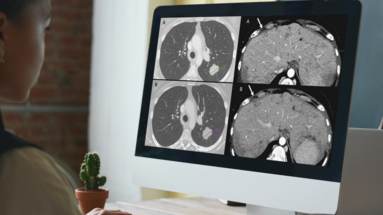

Advancing Neuro-Oncology Assessments: Mint Medical to Integrate Newly Published RANO 2.0 Criteria into mint Lesion™

Glioblastomas and other gliomas are the most common malignant primary brain tumor types, yet few effective therapies are available. Clinical research and clinical trials are essential in supporting…